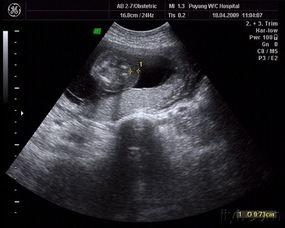

在这个阶段,宝宝的身长大约在20-25厘米左右,体重也在逐渐增加。虽然宝宝还是个小不点,但他的轮廓已经非常明显了。你可以通过以下这张图片来感受一下宝宝的体型变化:

五个月的宝宝,他的心脏、肝脏、肾脏等器官都已经发育得相当完善。而且,宝宝的眼睛、耳朵、鼻子等感官器官也在逐渐成熟。以下这张图片展示了宝宝内部器官的发育情况:

以下这张图片展示了宝宝在妈妈肚子里的胎动情况: